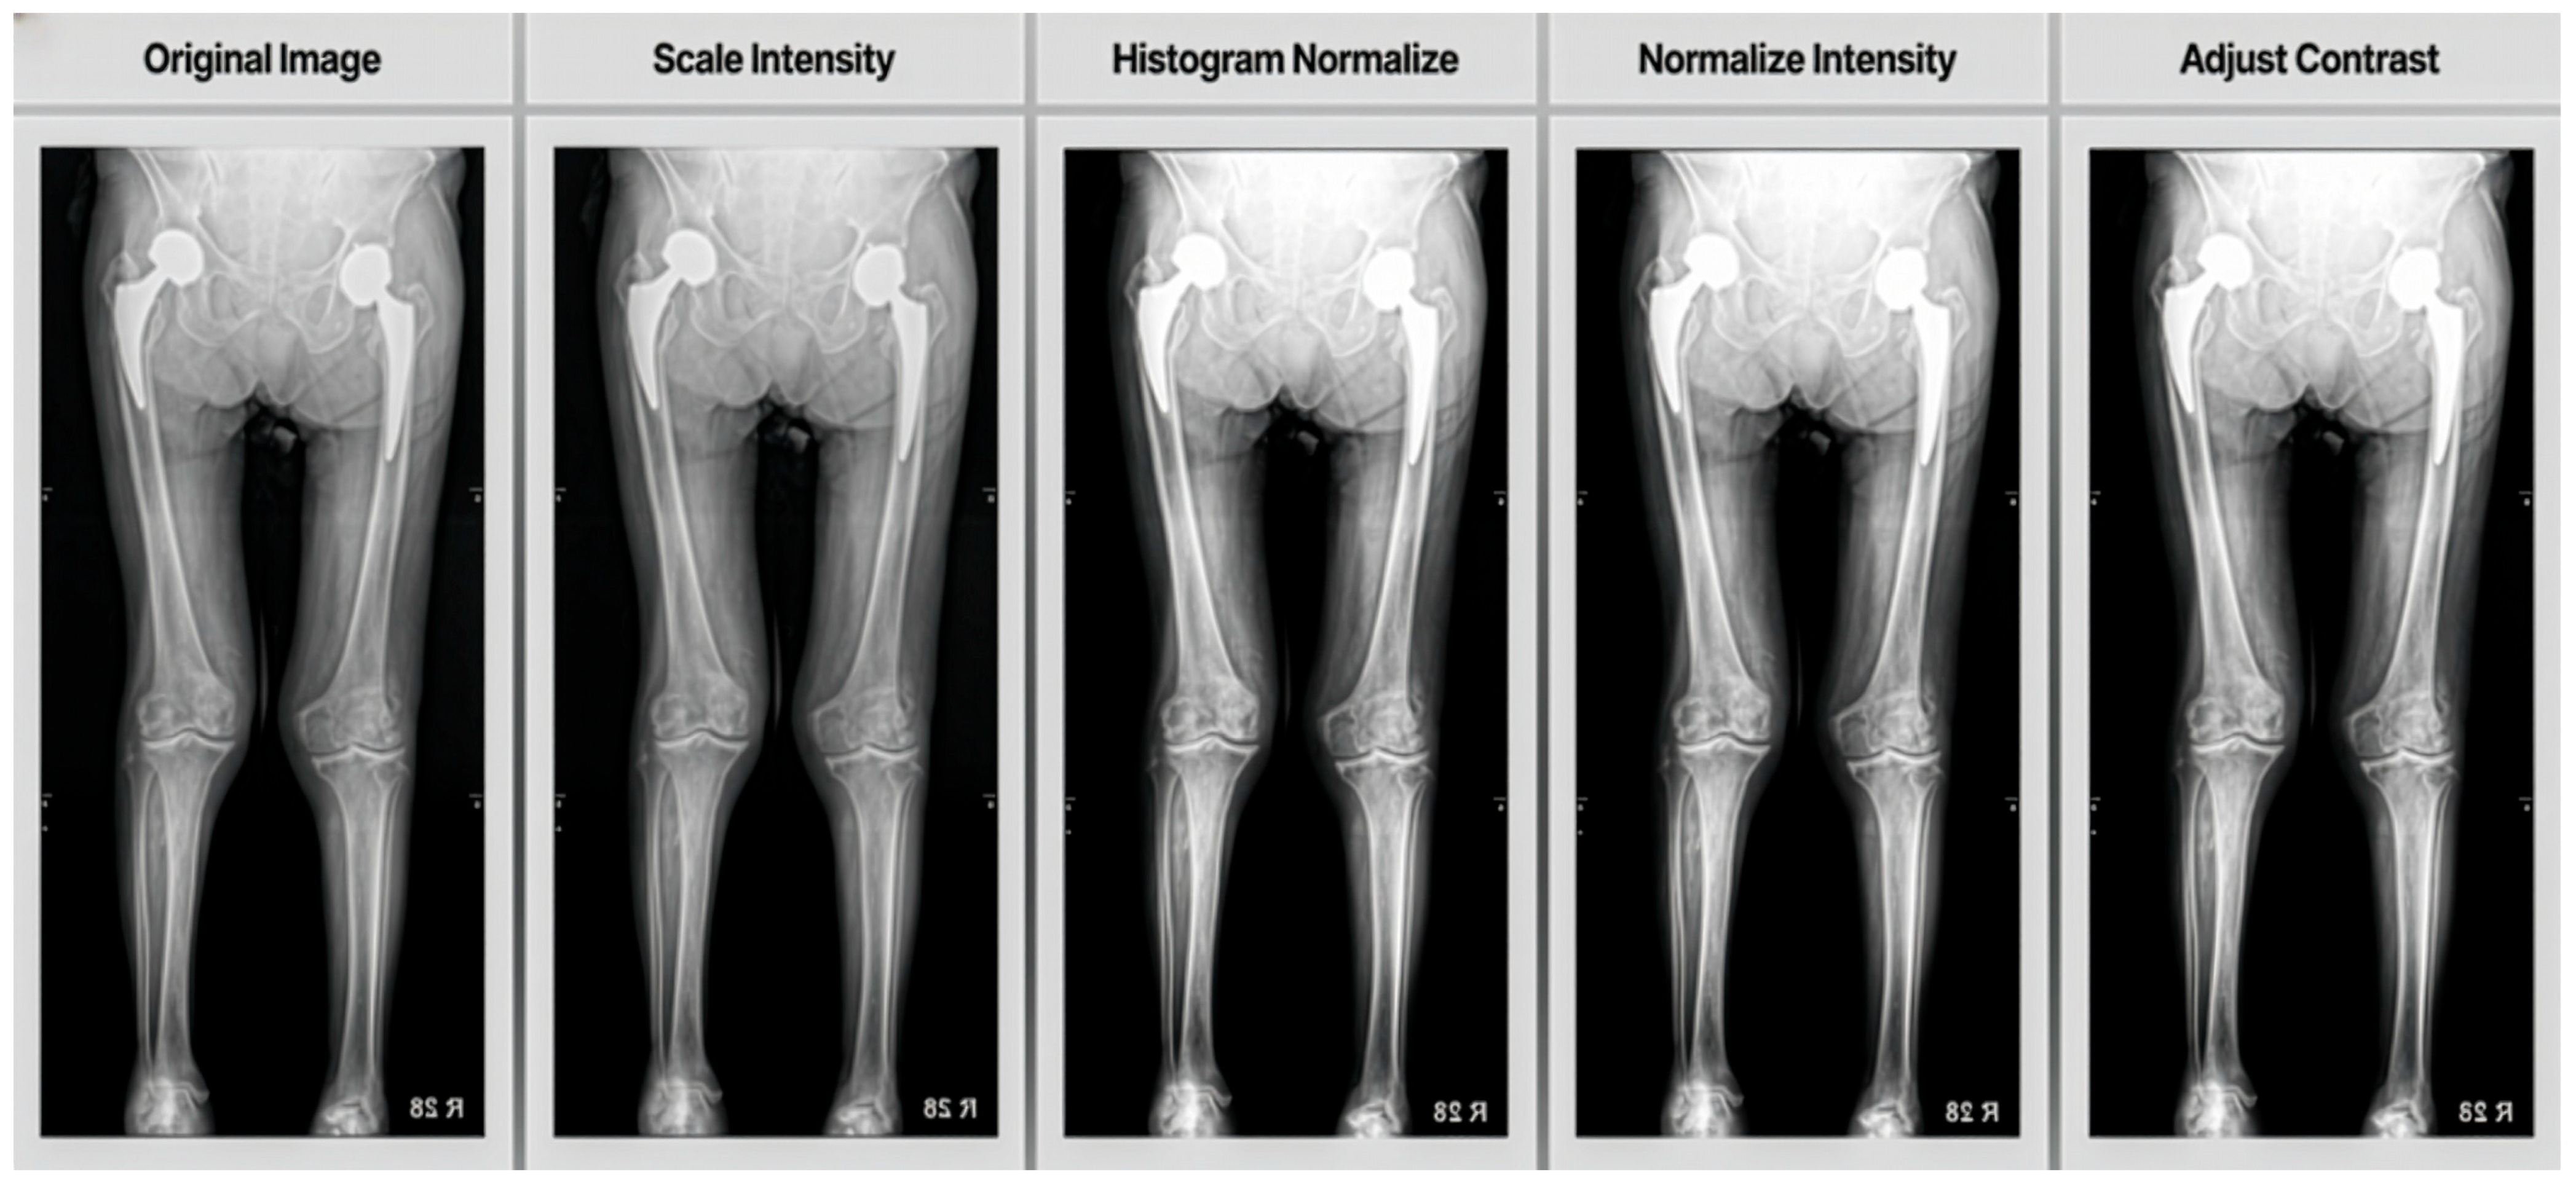

• Scale Intensity (min = 0.0, max = 1.0): This transform scales the intensity values of the image to a range between 0.0 and 1.0. Normalizing the intensity range helps standardize the input data across different images, which can improve the model’s learning process and performance.

• Histogram Normalize: Histogram normalization is applied to enhance image contrast. This technique redistributes the intensity values of the image to convert the full range of possible intensities more evenly. It can help in making features more distinguishable, especially in medical imaging where contrast can be critical for identifying structures.

• Normalize Intensity: Standardized input data by subtracting the mean and dividing by the standard deviation of image intensities, aiding faster convergence and improved performance.

• Adjust Contrast (gamma = 1.6): Gamma correction was used to increase contrast, making darker regions darker and brighter regions brighter, which enhances image features.

As shown in Figure 3, these pre-processing steps work together to standardize the input data, enhance important features and improve the overall quality of the images before they are fed into the neural network for training. Crucially, all these pre-processing procedures, including image resizing and random horizontal flipping, were rigorously standardized. Each step was applied consistently to every image using the same predefined algorithms and parameters (e.g., Scale Intensity to min = 0.0, max = 1.0; Adjust Contrast with gamma = 1.6). This entire process was fully automated and executed via programmatic scripts, ensuring an entirely objective approach without any human intervention or subjective judgment.

Figure 3. To prepare the X-ray images for segmentation, four key pre-processing steps were applied: intensity values were first scaled to a 0.0–1.0 range to ensure consistent brightness; histogram normalization redistributed pixel intensities for enhanced contrast; subsequent intensity normalization (subtracting the mean and dividing by the standard deviation) further standardized the data; and finally, gamma correction (γ = 1.6) adjusted contrast to emphasize important anatomical features.